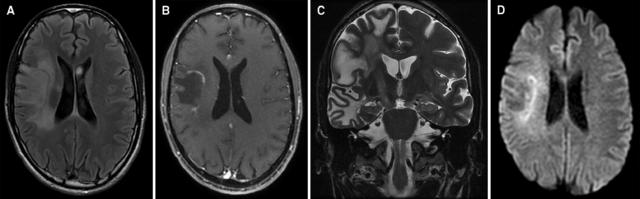

案例 7:47 岁女性,诊断为亚历山大病。

图 8 A~C:FLAIR 可见延髓萎缩伴皮质脊髓束投射区高信号,双侧深部小脑白质和大脑半球高信号;D:T1 增强可见延髓和上颈髓萎缩

案例 8:60 岁男性,诊断为亚历山大病。

图 9 T2WI 可见明显的延髓萎缩 [a] 伴轻度小脑萎缩 [a~b],但脑桥基底部基本正常 [b],四脑室稍扩大 [b],中脑,特别是背侧,可见萎缩 [c];l:矢状位 T1WI 可见典型的蝌蚪状脑干萎缩,包括明显的颈髓-延髓萎缩,脑桥基底部完整,需注意,中脑被盖萎缩同样促成了「蝌蚪」的形成

案例 9:48 岁男性,诊断为白质消融性白质脑病。

图 10 A~B:T2WI 和 FLAIR 可见双侧弥漫白质高信号,累及 U 形纤维,内囊和外囊,伴深部白质空泡化